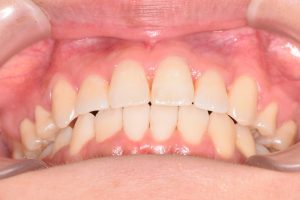

初診時(2022年12月)と装置撤去時(2025年9月)の写真です。

正面

問題点

・叢生

・右上犬歯低位唇側転位

・下顎骨の後方位による上顎前突

・下顎前歯部唇側傾斜

・右側第二大臼歯部シザーズバイト

両側の犬歯が咬みあっていないので

奥歯にとても負担のかかる咬合状態でした。